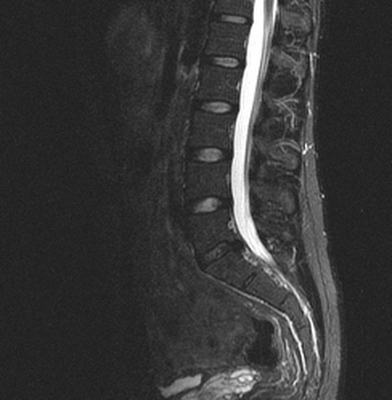

Множественные (2) гемангиомы на МРТ грудного отдела позвоночника

Грудной отдел позвоночника на МРТ в коронарной проекции